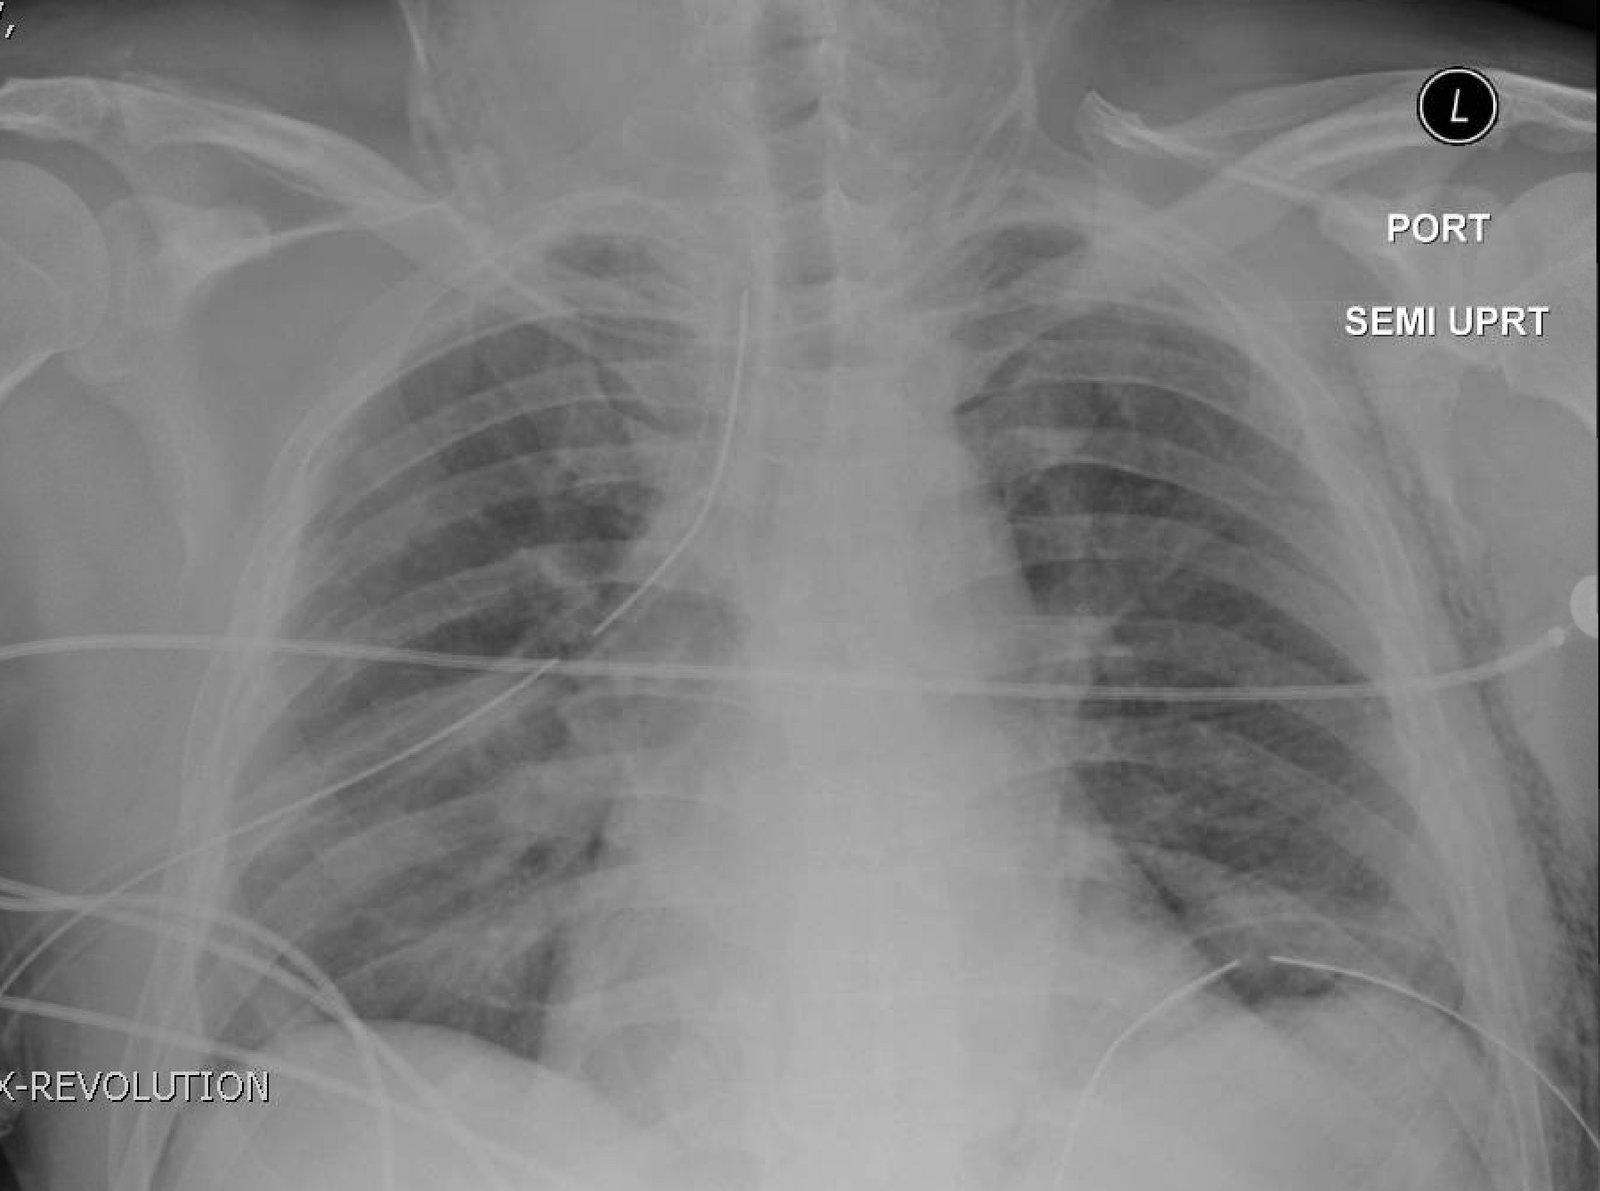

Plain film anteroposterior (AP) radiography of the chest shows left-sided subcutaneous emphysema (red arrow) with overlapping muscle striations of the pectoralis major (green arrow). After chest tube placement (blue arrow), AP chest radiography shows persistent left-sided subcutaneous emphysema (red arrow). CT of the chest shows pneumomediastinum (blue arrow), left apical pneumothorax (pink arrow), and subcutaneous emphysema (red arrow) at the level of T2. At the level of T6, rib fractures can be visualized on the CT (yellow arrow). At the level of T8, left sided pneumothorax is also seen (pink arrow) as the absence of lung tissue on CT.